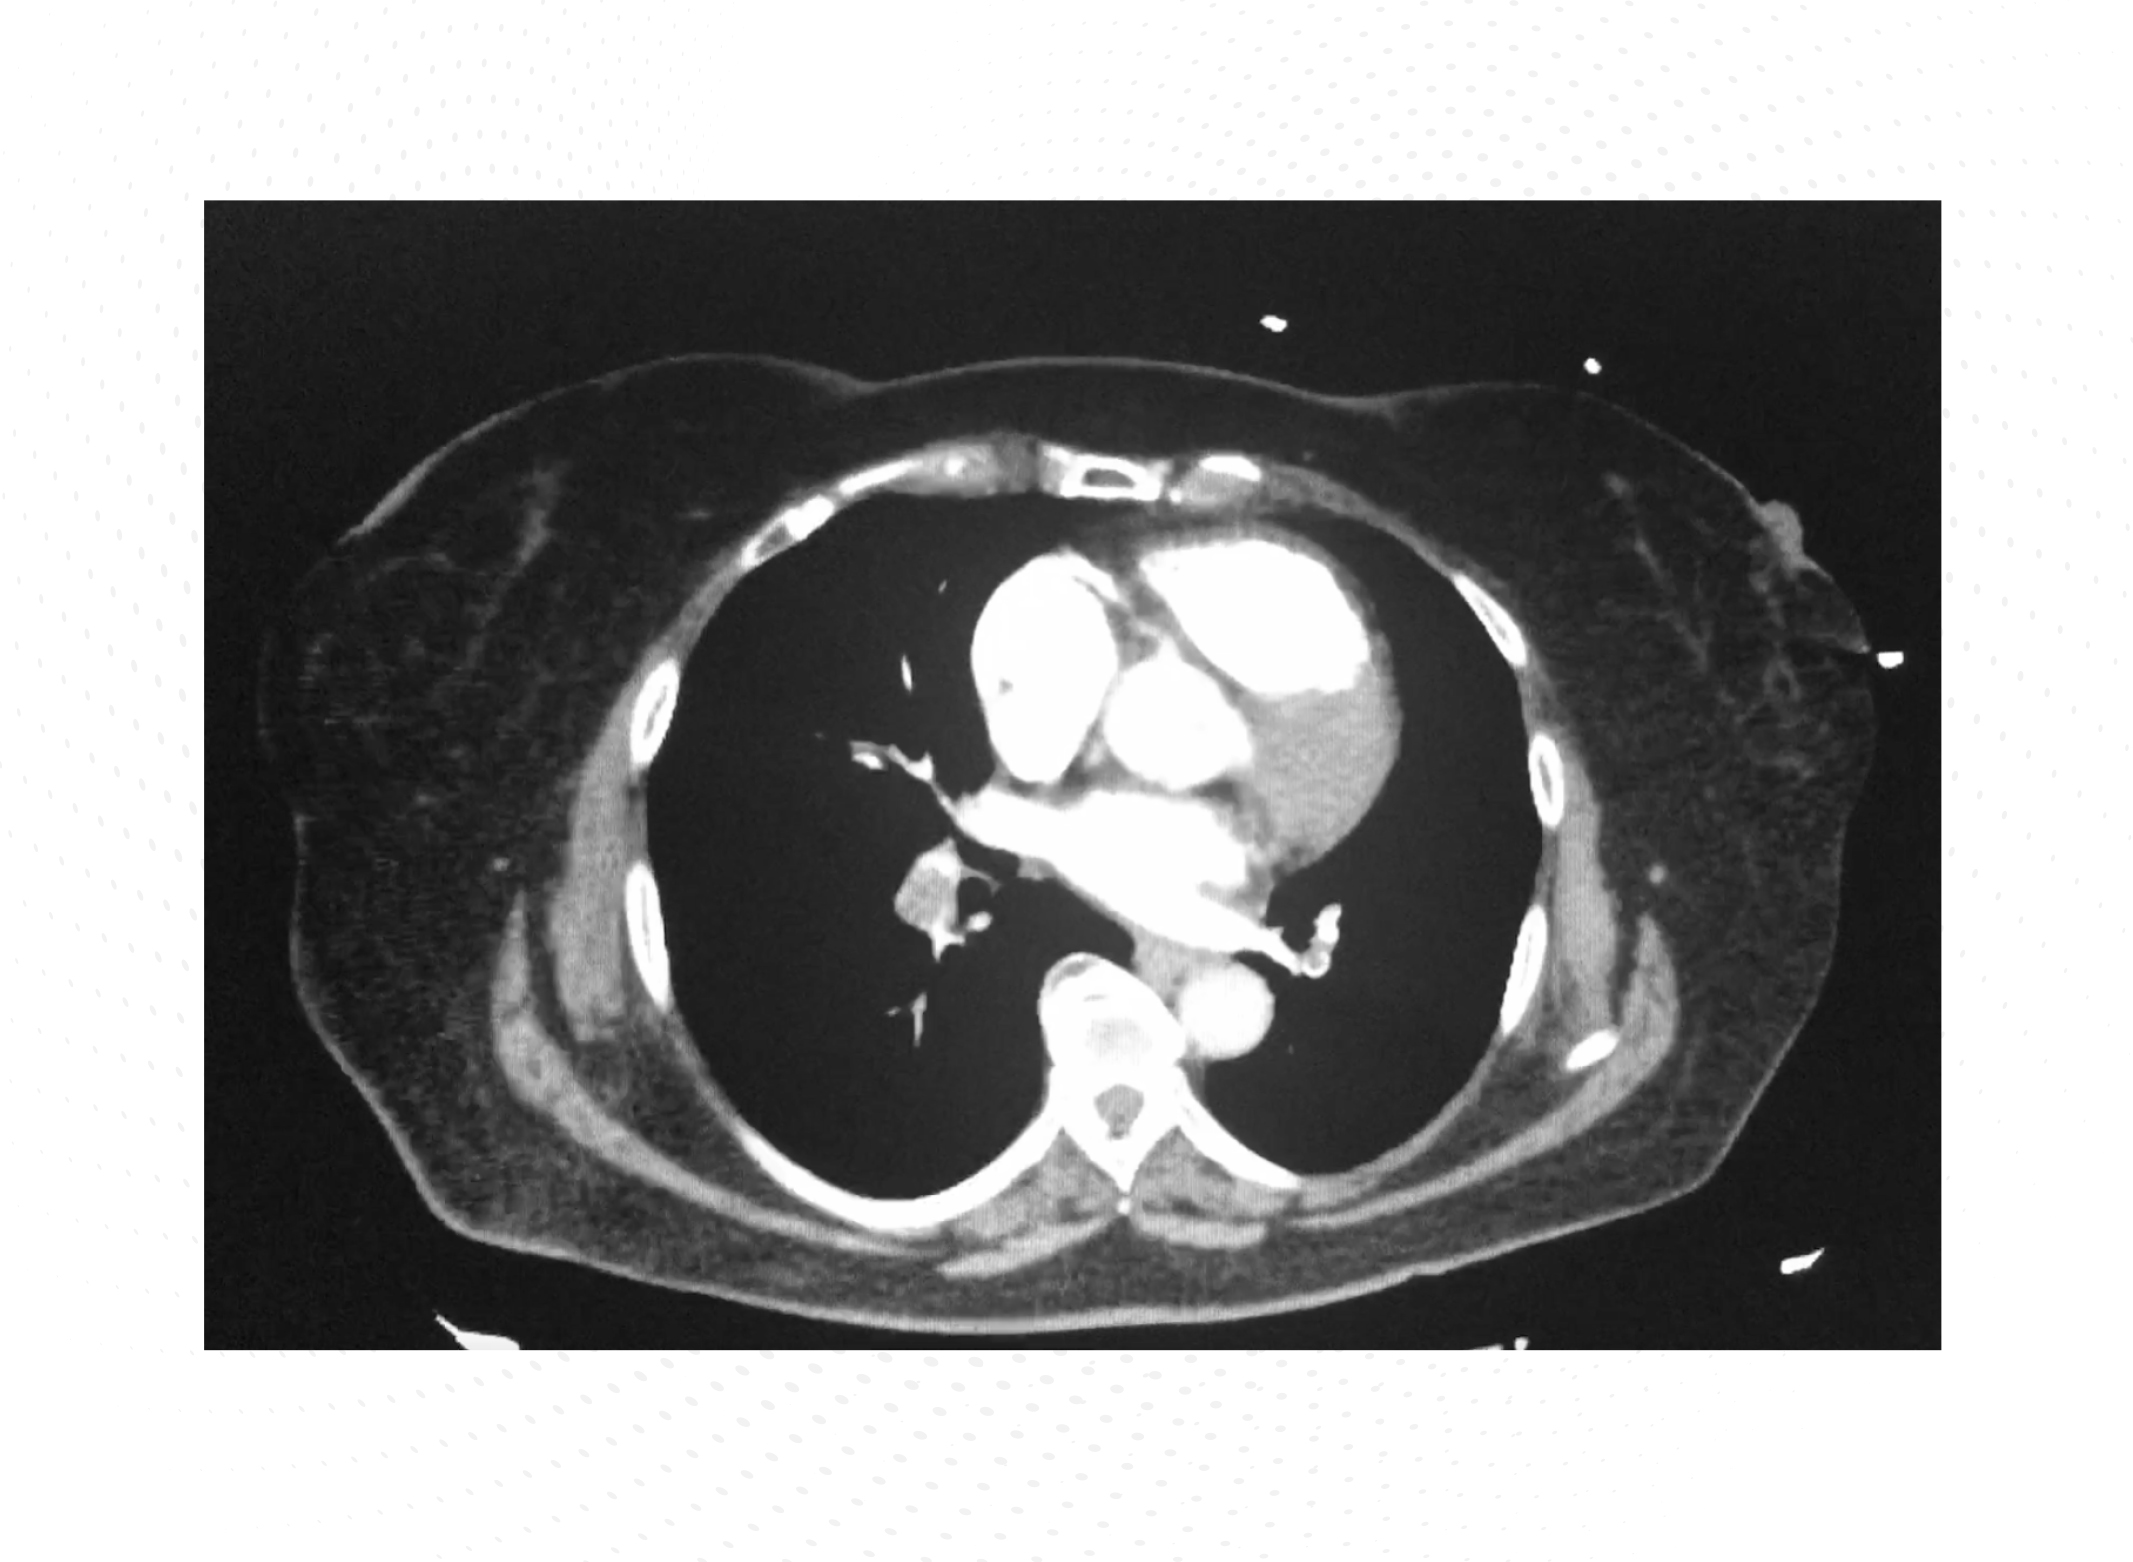

En la endoscopia oral se encontraron 2 úlceras cubiertas por fibrina y un tumor ulceroso semicircular de 5 cm en el duodeno. En el examen histológico, se diagnosticó un linfoma de grado alto positivo para CD20, tanto en el nódulo linfático como en las muestras de biopsia mesentérica y endoscópica. Tras la valoración por el Servicio de Hematología, se recomendó tratamiento con 6 ciclos del régimen R-CHOP (rituximab, ciclofosfamida, doxorubicina, vincristina y prednisona) cada 14 días, seguido de 2 ciclos adicionales de rituximab. Los primeros 2 ciclos de R-CHOP-14 fueron bien tolerados y el paciente mejoró de forma significativa. Sin embargo, cuando el paciente acudió al hospital de día para realizarse el tercer ciclo de quimioterapia, manifestó cuadro de dolor torácico y disnea de 2 días de evolución, por lo que se derivó al Servicio de Urgencias para la realización de una angiotomografía axial computarizada (angio-TAC) de tórax urgente. La TAC reveló un embolismo pulmonar (EP) bilateral con afectación bibasal Figura 1.